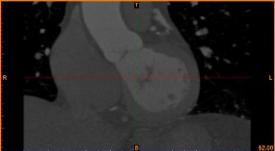

首先通過病人的心臟冠脈造影CT數(shù)據(jù),獲取病人的心臟冠脈三維模型。

病人的冠脈造影CT數(shù)據(jù) 提取出的冠脈三維數(shù)據(jù)